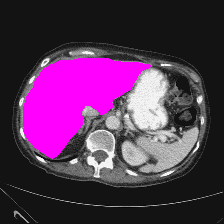

| (a) Ground Truth | (b) Prediction | (c) Heatmap |

In this thorough comparison with top-tier models, our methodology underscores its superiority. To emphasize, the Dice Similarity Coefficient (DSC) of our proposal impressively settles at 82.16%, outclassing formidable contenders like the HiFormer, which rests at 80.39%.

A salient feature of our model is its aptitude for delineating finer anatomical structures. The integration of ISIM markedly amplifies this capability. This prowess is evident in the Gallbladder’s segmentation, where our technique delivers a 71.48% score, overtaking others like the TransDeepLab’s 69.16%. Similarly, the Pancreas, a traditionally intricate organ to segment due to its size, witnesses a conspicuous uplift with our method, achieving 65.02%, surpassing even the FFUNet-trans’s 64.17%.

In the segmentation of more pronounced organs, our model remains unparalleled. The Kidney (L) and Kidney (R) respectively logged scores of 85.45% and 80.85%. Noteworthy is the Liver’s segmentation, where our approach, with a score of 94.85%, nearly mirrors the HiFormer’s 94.61%. Furthermore, in segmenting the Spleen, our model, at 91.62%, slightly edges out our own baseline, which clocked 91.05%.

Reinforcing our point on the model’s capability to harness long-range information, it’s imperative to note our method’s adeptness in segmenting both small and large organs. This demands a considerable receptive field size for precision in object prediction. We further elucidate this with a class activation map for both organ types in Figure 4, shedding light on our model’s enhanced ability to discern local patterns, resulting in meticulous segmentation.